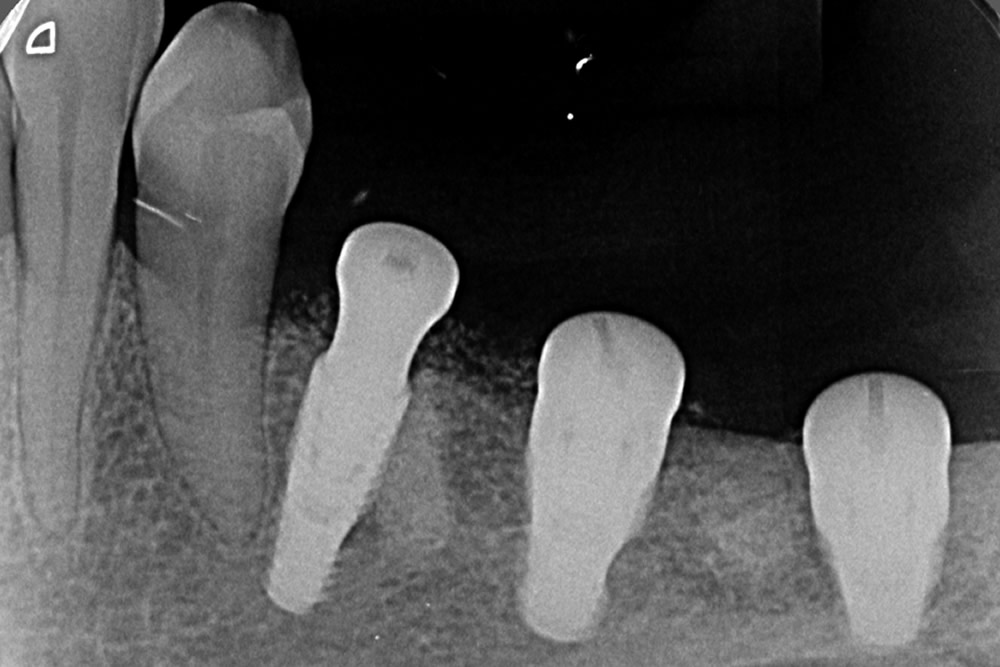

Cada planejamento é único e individual, baseado sempre em exame clínico e exames complementares (exames radiográficos, fotografias, tomografia computadorizada, enceramento de diagnóstico, etc.).

Próteses Fixa sobre implante

É utilizada para substituir ,através de implantes intra-ósseo, dentes já condenados que foram, ou ainda precisam ser extraídos. É a melhor opção capaz de restabelecer função mastigatória, conforto e estética, seja em casos de reabilitação de um único dente ou até de uma arcada dentária inteira (protocolo). As próteses sobre implante podem ser produzidas com diversos materiais, e esta escolha se torna fundamental para um resultado estético favorável.